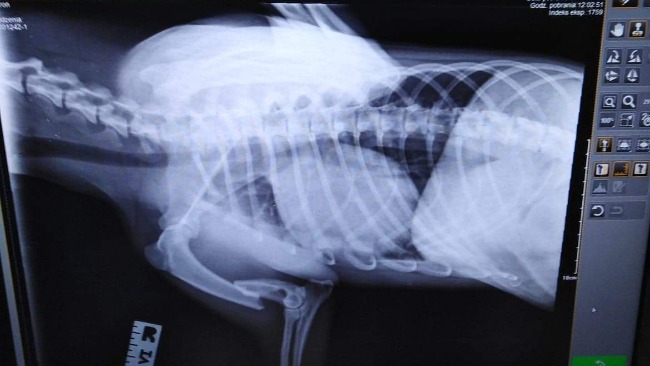

Witam, zbieram na operację dla mojego psa Arona. Piesek podczas spaceru wpadł w dziurę i złamał łapkę. Podczas wizyty u weterynarza dowiedzieliśmy się że pies potrzebuje jak najszybszej operacji, która kosztuje 1500zł. Nie ukrywam, że jest to zbyt duża kwota jak na krótki czas. Jeśli ktoś byłby chętny i w stanie wpłacić chociaż złotówkę to byłabym ogromnie wdzięczna.